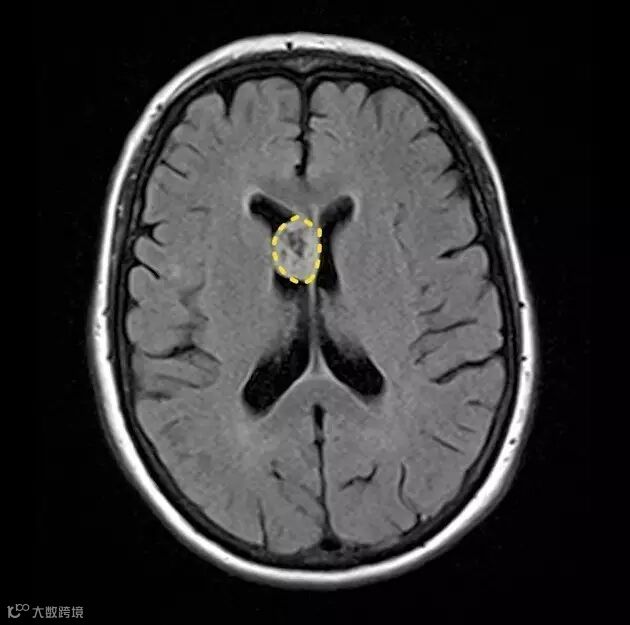

FLAIR